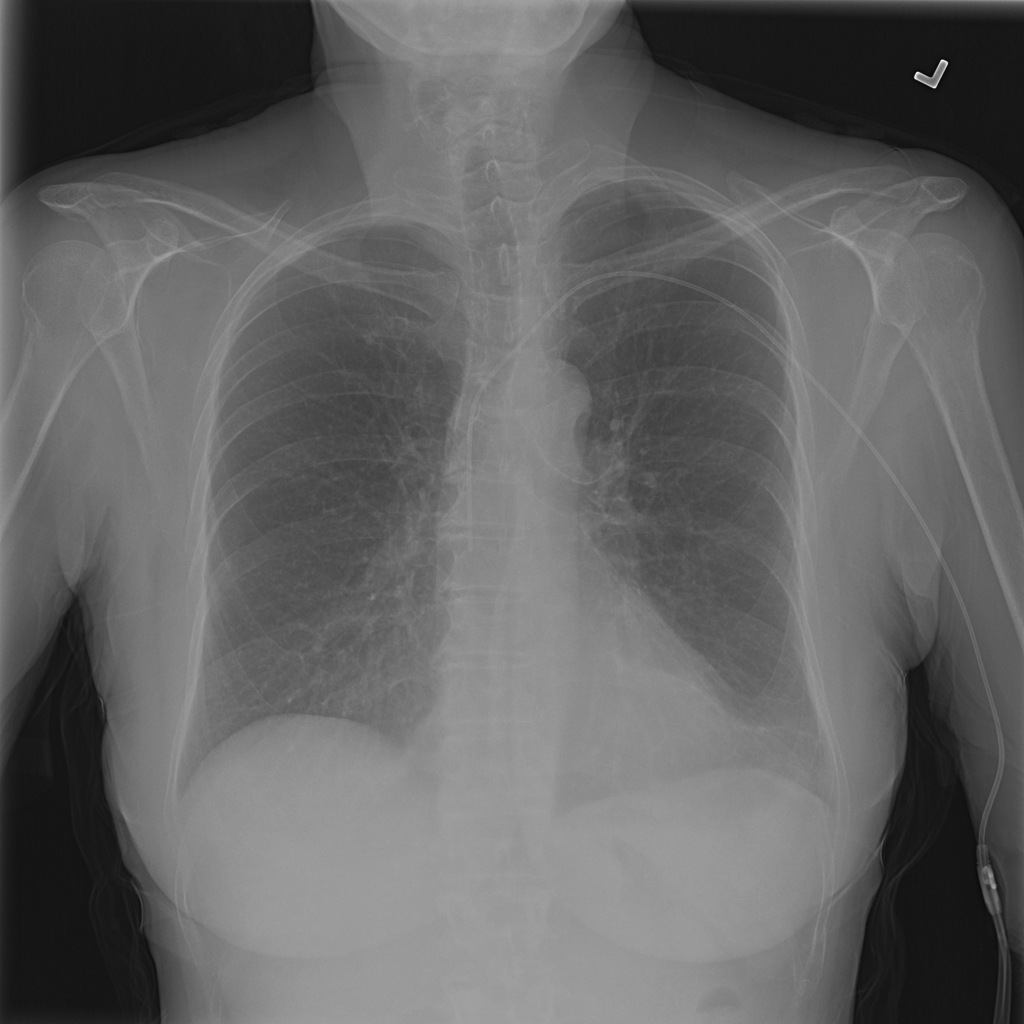

PAT-3384 · IMG-054Atelectasis

PAT-3384 · IMG-054

AP